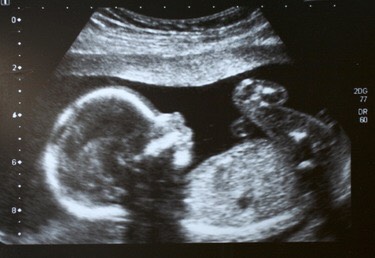

Девочки, вот интересно, ваши малыши на фото УЗИ и после рождения похожи были?

Я обычное УЗИ делала(не 3Д) там он в профиле лежит)очень похож))

Я делала для себя еще узи в 38 недель и родила в 38,были прям как копия на фото

А говорят ещё, что они все одинаковые на этих фотках(

Похожи))Я делала именно только лицо в 6 мес,была похожа))

В 18 недель))второй скрининг)